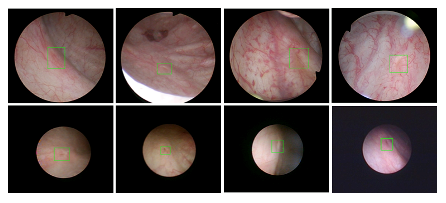

beat365中文登录入口医疗机器人研究院—深睿医疗人工智能医学视频联合实验室成立于2018年7月。PI包括来自于交大生医工学院和电院的三位教授,平台建设目标是将人工智能实时地用到临床医学中去,研究方向包括:1. 建立内窥镜人工智能辅助诊断系统,通过对病灶和解剖结构的实时识别来辅助医生更好地进行微创诊断和治疗;2. 以个性化、定量化的精准诊疗技术为研发目标,重点开展医学影像智能诊断、医学可视化及计算机辅助手术规划、AI及大数据分析在临床诊疗流程中的集成应用等方向的研发。试图利用AI技术、大数据分析技术、3D打印技术、虚拟现实及增强现实技术促进临床的影像诊断、治疗方案设计、预后预测分析等诊疗环节的智能化提升与技术变革;3. 面向运动医学康复、神经退行性疾病量化诊断,以及其他与人体运动相关的疾病诊疗、康复应用,开展视觉三维人体运动的测量、分析与识别研究,通过基于深度学习的视觉检测识别以及相关大数据分析,为相关疾病的诊疗和康复提供AI辅助。具体临床应用包括:关节镜手术术后康复指导和评估、帕金森病的量化诊断、精神疾病的量化诊断与评估、儿童异常行为分析等。

近年来,联合实验室发展了泌尿镜手术实时识别技术,人体姿态精确识别技术,另外围绕小儿先心病手术、肝癌消融手术、数字口腔诊疗的智能化提升等内容进行应用研发。